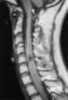

Extramedullary intradural signal void

May Be Caused by

Acute hemorrhage

Arteriovenous malformation

Intracranial air

Lumbar puncture